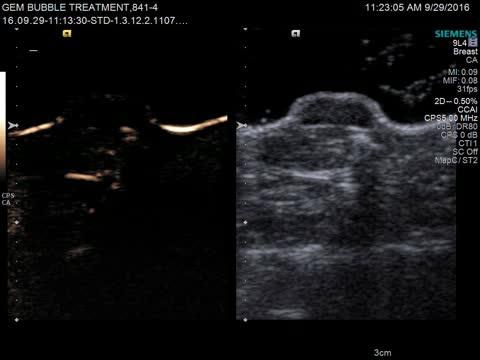

Figure 2 from Ultrasound-mediated microbubble destruction: a new method ...